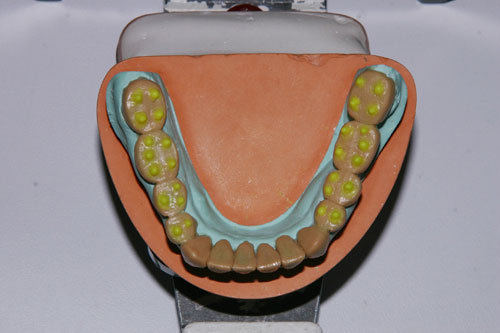

Pitombos en Disclusión Inicial

Alineación Tridimensional Sup.

Alineación Tridimensional Inf.